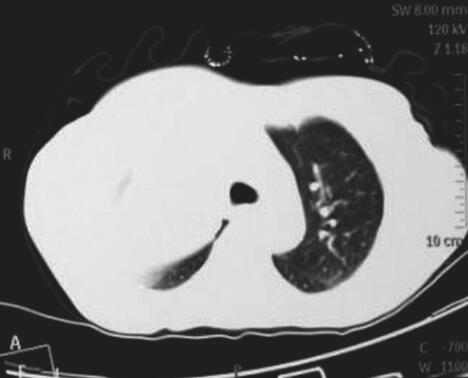

图4 肺部CT

右肺上叶阻塞性肺不张,左肺团块影,周围见片状渗出影,较前增大